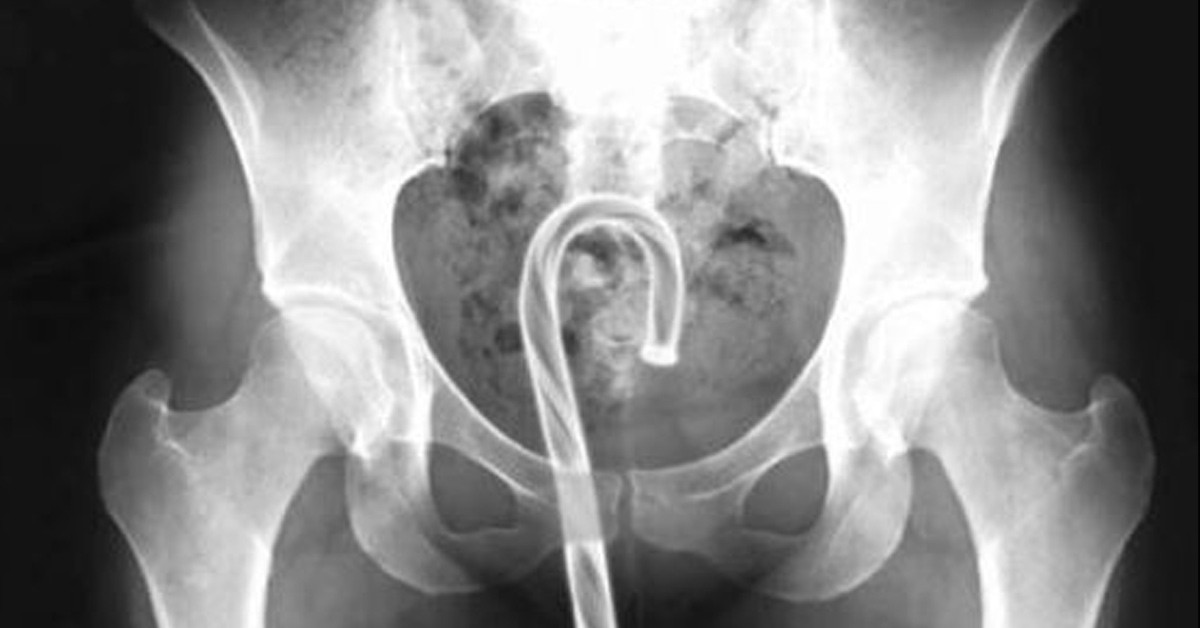

Bu şişe nasıl oraya girmiş olabilir ki?